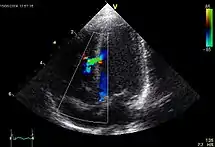

- Ехокардіографія — Візуалізується вентрикулосептальний дефект, декстрапозиція аорти та обструкція вивідного тракту правого шлуночку